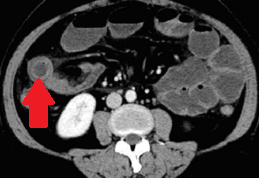

CT Scan. The gastric tumors are obvious (red arrow). Incidental finding right sided sizable renal cysts (blue arrow)